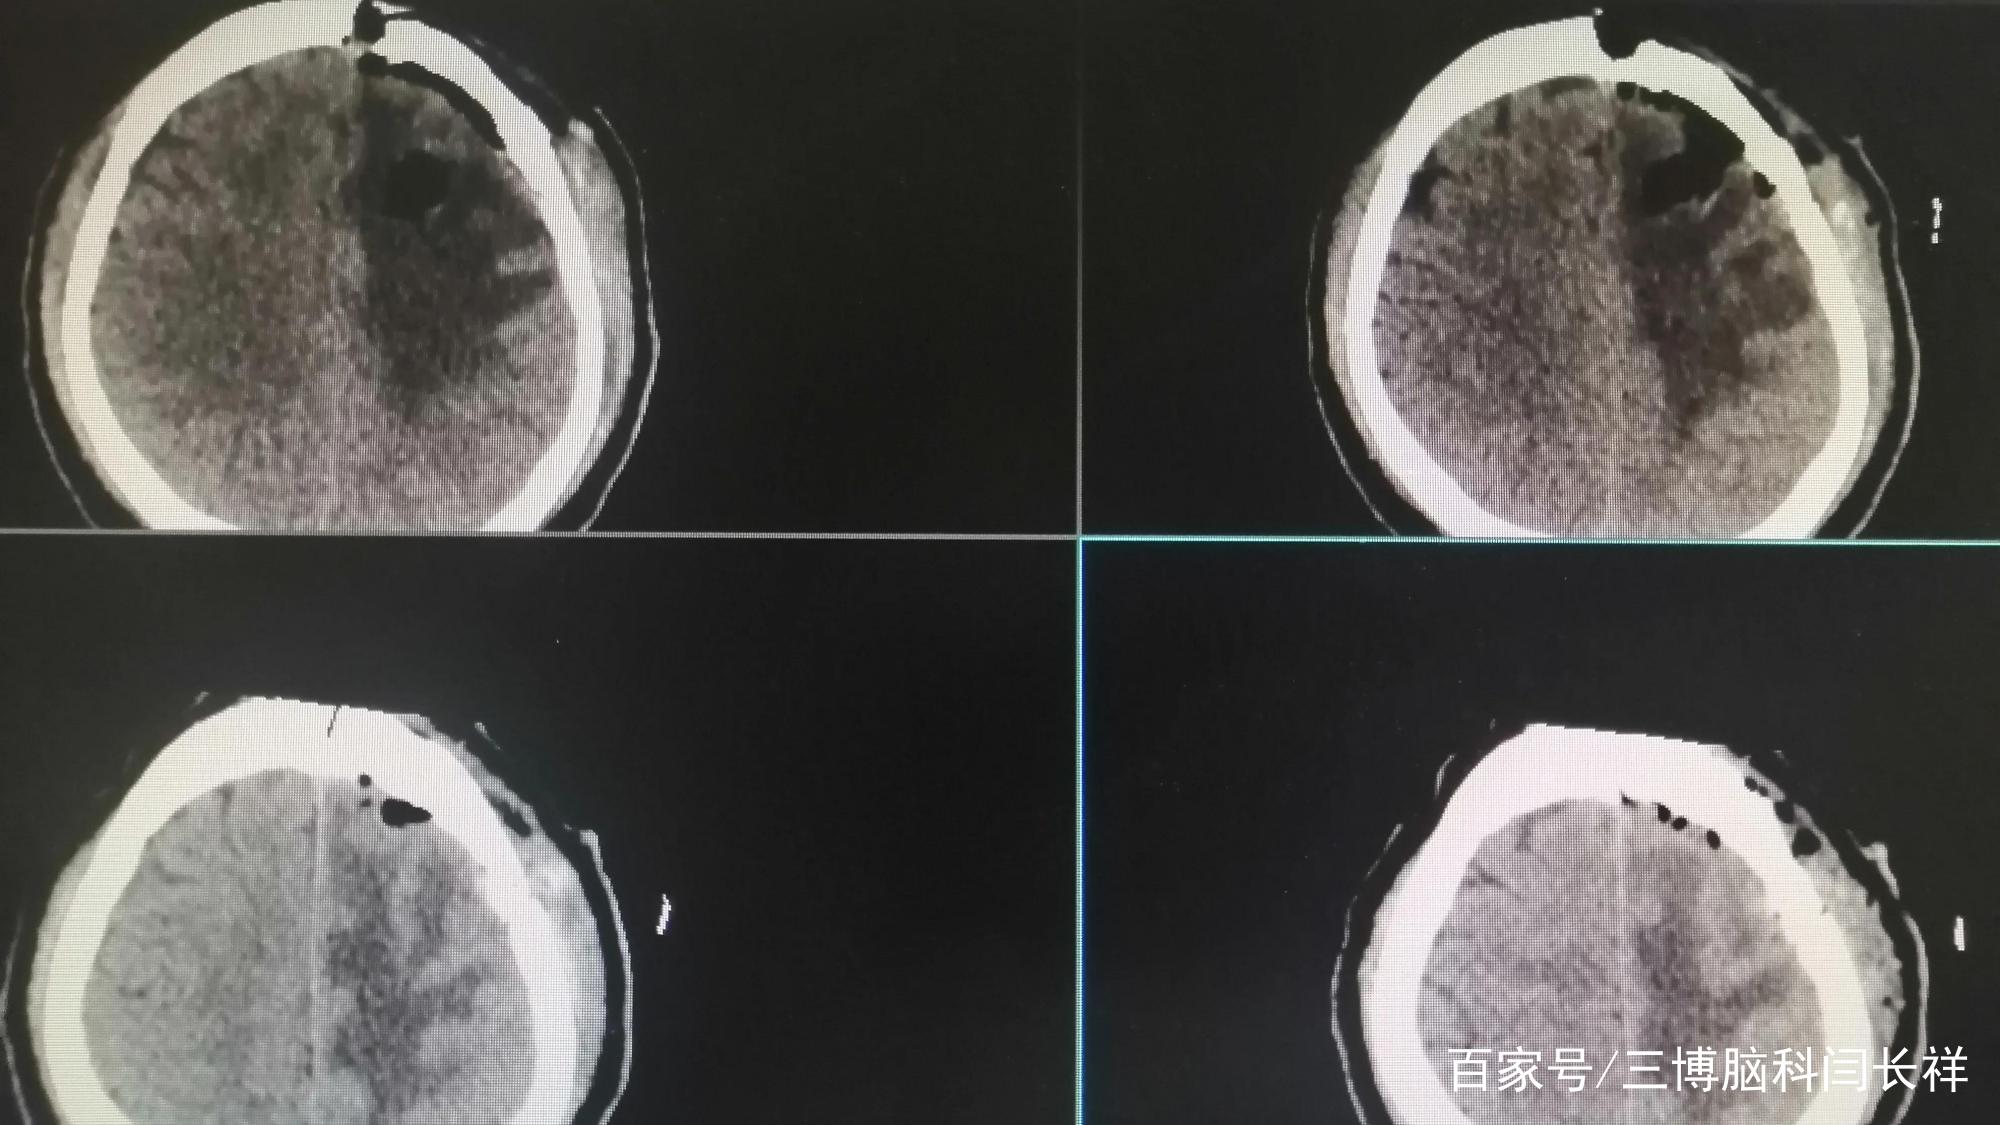

初步诊断:左额胶质瘤。

左侧大脑掌管右侧肢体活动,就是因为左额这里长了肿瘤,所以才导致老孙右脚踩刹车像是演慢动作,这是因为腿脚不灵便了呀,反应力变差。说话变慢也是同样的道理。

6月29号,老孙于全麻下行左额开颅肿瘤切除术。手术顺利。